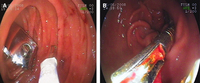

(A) Visão endoscópica de um cortador de unhas impactado no duodeno. (B) Remoção endoscópica de um prendedor de gravata

De: Canda AE. BMJ Case Reports. 2009;2009:bcr12.2008.1354